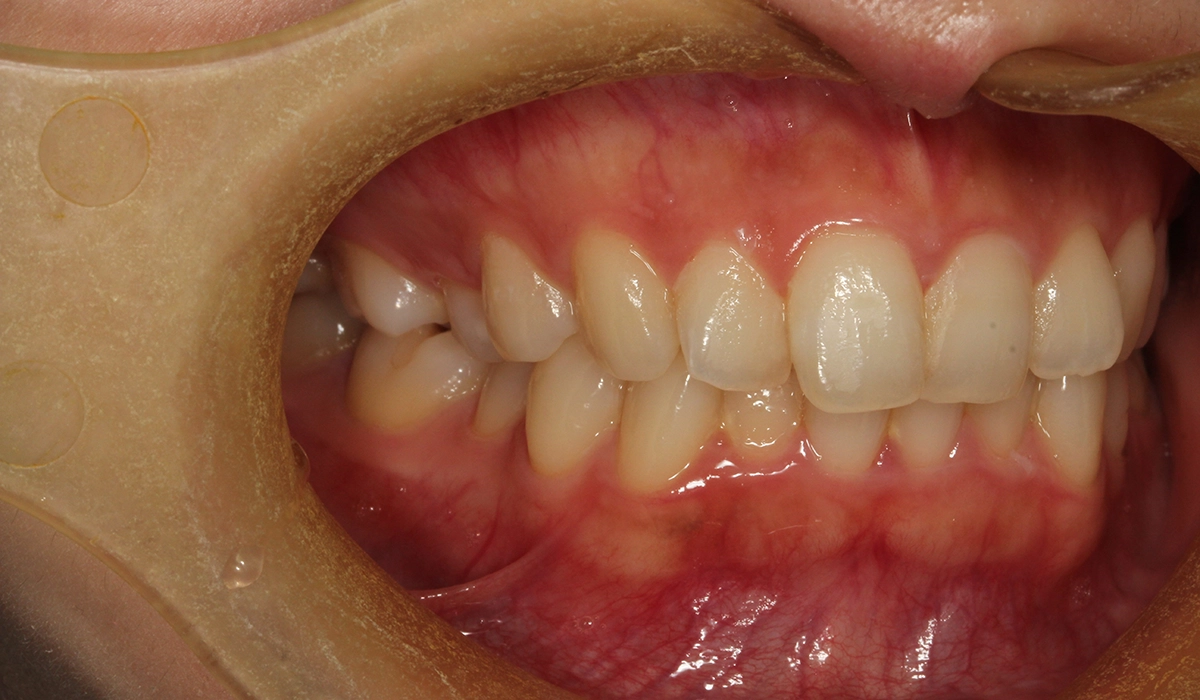

術前:右側

今回ご紹介する患者様は、全体的な歯列のがたつきを気にされており、検査後Ⅰ級叢生と診断。

非抜歯と可能な限りIPRなしにこだわったため、大臼歯の遠心移動を主体としてスペースを確保したため治療期間がやや長くなるも18カ月で完了致しました。